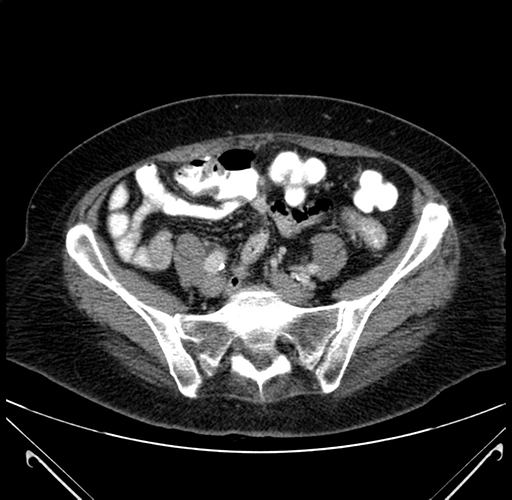

Pre-Chemo: Axial Venous

Axial Venous